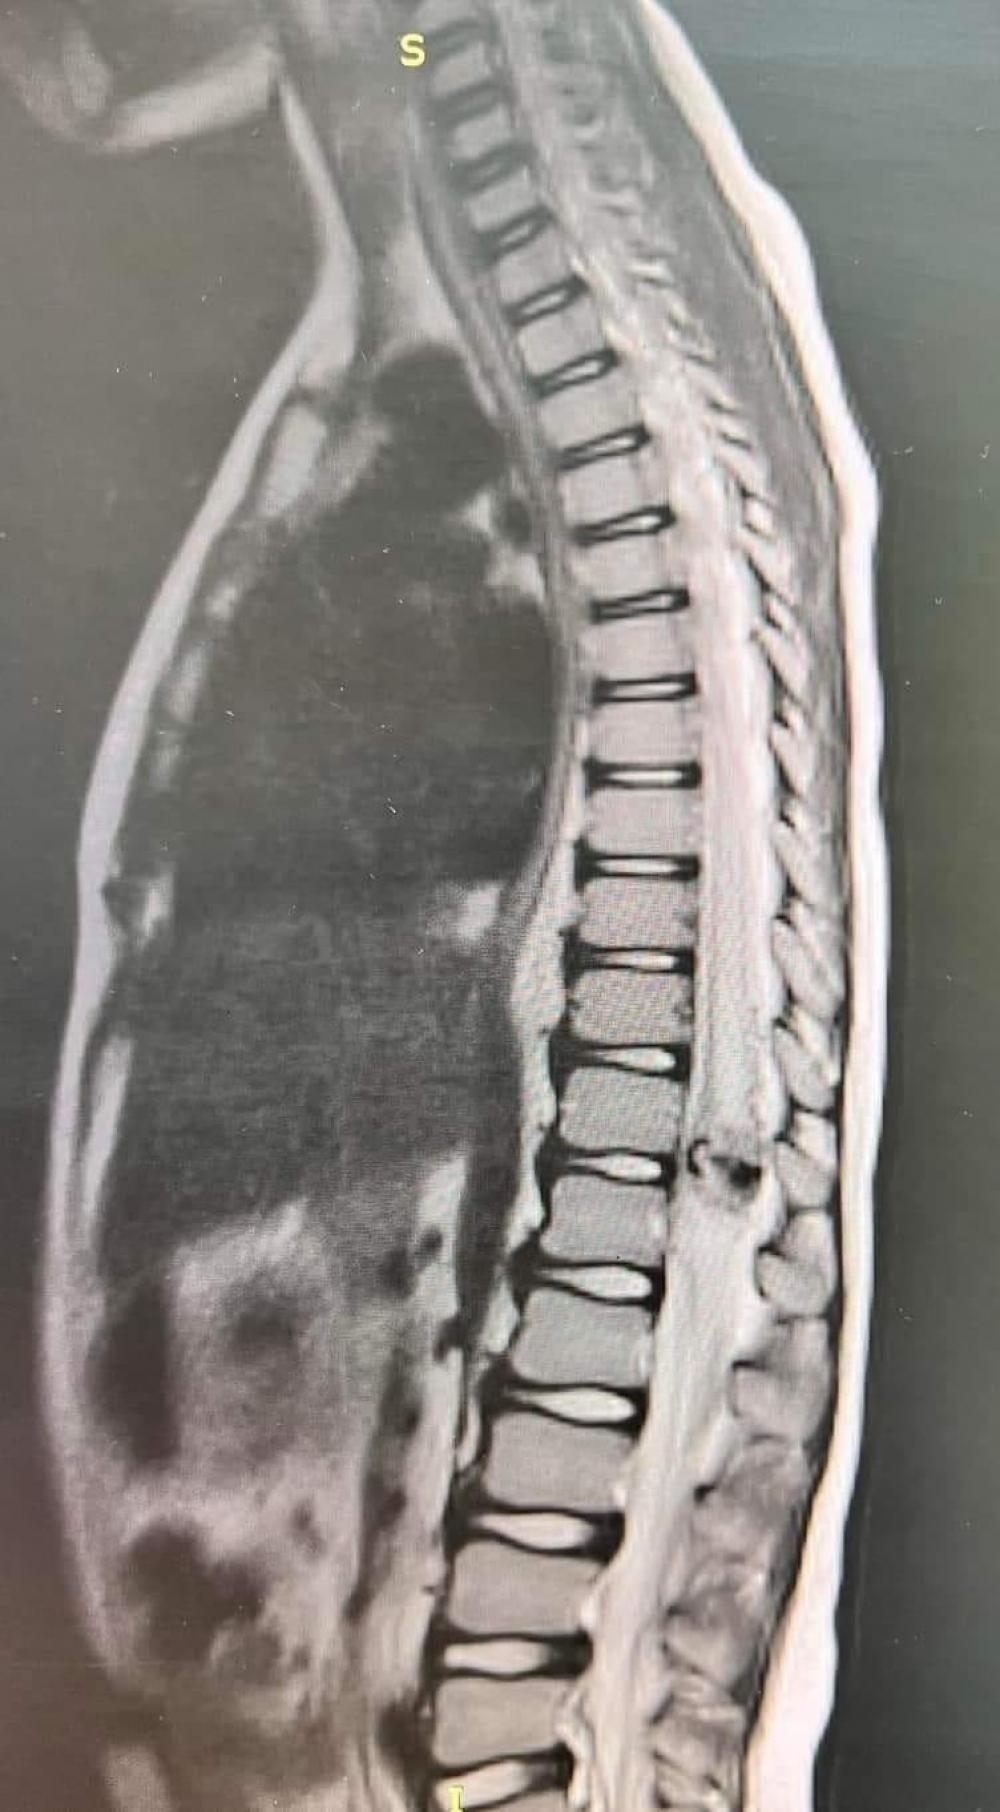

У сина загиблого Героя з Острога Дмитра Боганця діагностували рідкісну патологію спинного мозку, через яку дитина втратила здатність ходити. Місяць тому Євгена прооперували у львівській лікарні святого Миколая.